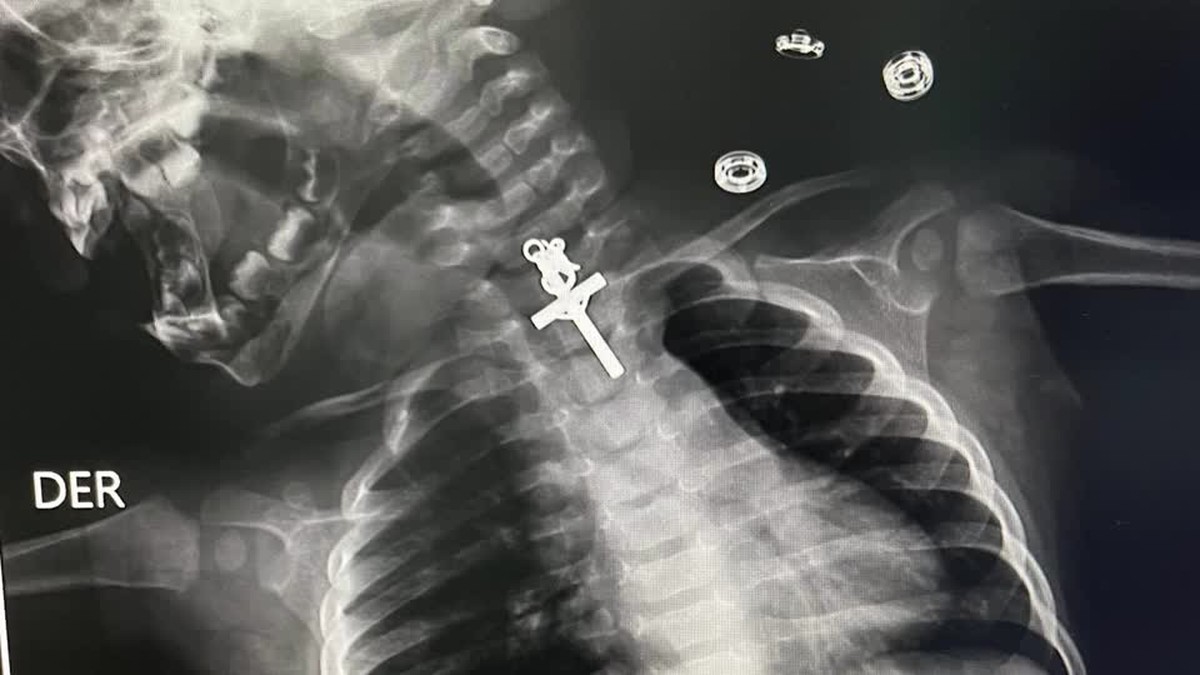

Exame de raio-x revela crucifixo preso dentro de garganta de bebê, no Peru